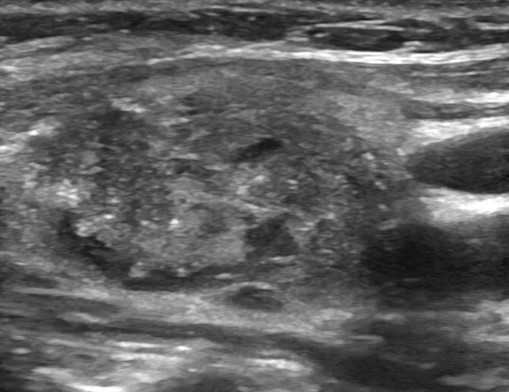

Образования, узлы. Во время сканирования доктор оценивает очаговую патологию и делает заключение в предположительном ключе. УЗИ щитовидной железы показывает:

Дифференциация опирается не только на серошкальные изображения, но и на данные ЦДК.

Опухолевое поражение на сонограмме

По результатам УЗИ врач может предположить характер новообразования.

Рак щитовидной железы на сонограммах имеет:

- неоднородную преимущественно гипоэхогенную структуру,

- неправильную форму;

- размеры свыше 1 см - новообразования более 4 см всегда подозрительны на малигнизацию;

- множественные кисты/узлы, участки отложения кальция, фиброз;

- рваные, размытые контуры.

Явная асимметрия долей, лимфаденопатия, инвазия опухоли через собственную капсулу в соседние ткани свидетельствуют о продвинутых стадиях болезни.

В режиме ЦДК при злокачественном новообразовании видна нарушенная архитектоника сосудистой сети, избыточное количество артерий и вен, зоны некроза.

На УЗИ с эластографией опухоль имеет большую плотность по сравнению со здоровыми тканями.